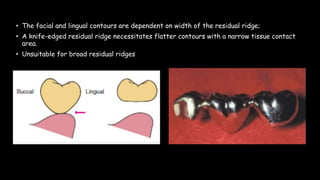

The document discusses pontic design for fixed dental prostheses. It covers pretreatment assessment of residual ridge contours, classifications of ridge deformities, surgical modification techniques, and ideal requirements for pontics. Pontic designs are classified based on their shape and materials. Factors in pontic selection include esthetics and oral hygiene. Common designs for anterior and posterior regions are described, including sanitary, ovate, and saddle pontics. Biological considerations for pontic design involve maintaining the residual ridge, abutment teeth, and supporting tissues.

![PONTIC DESIGN CLASSIFICATION

• According to Rosenstiel

A] MUCOSAL CONTACT:

1. Ridge lap

2. Modified ridge lap

3. Ovate

4. Conical

B) NO MUCOSAL CONTACT

1. Sanitary (hygienic)

2. Modified sanitary (hygienic)](https://image.slidesharecdn.com/ponticandponticdesigns-201011153902/85/Pontic-and-pontic-designs-23-320.jpg)